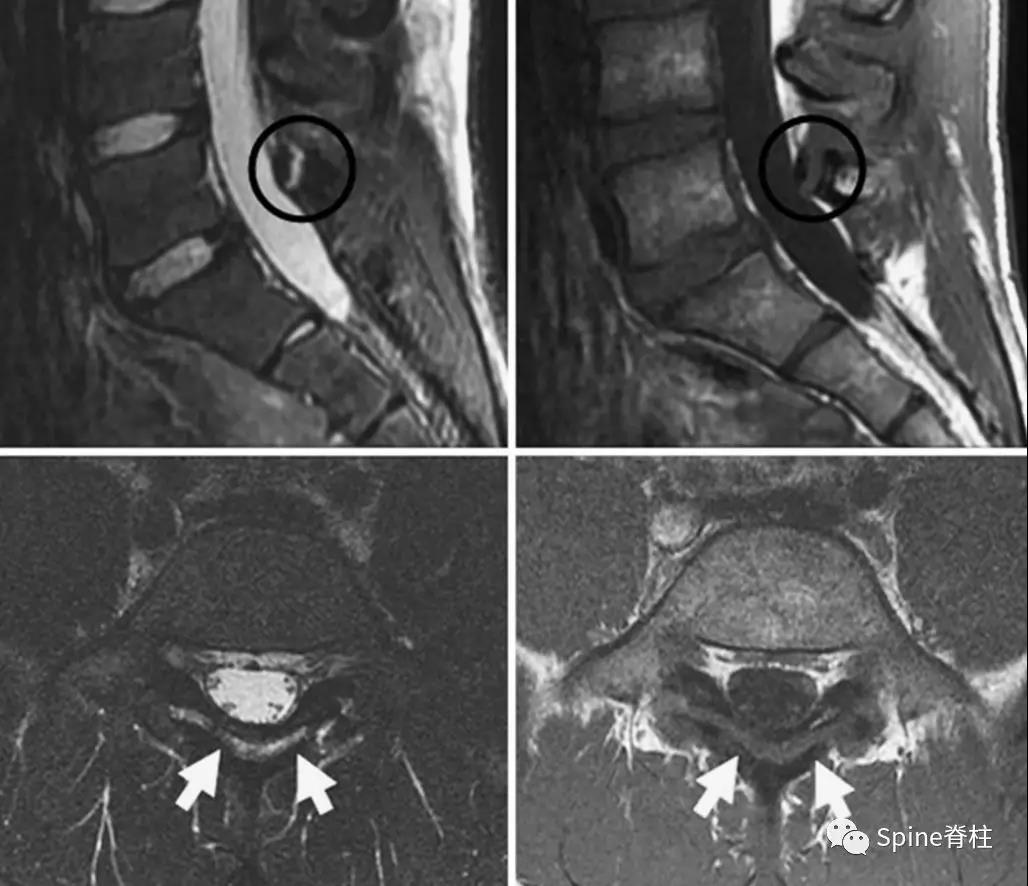

1. 椎弓根裂典型病例

一项来自Spine的临床研究发现,椎弓根裂是18岁以下常见的腰痛原因,发生率为12.7%,而峡部裂仅为8.7%。且椎弓根裂与腰椎前凸增加无关,常出现在13-17岁的腰痛患者,男性多于女性,常是孤立性出现的损伤(69.6%)。

图:15岁腰痛男孩,左侧腰5椎弓根裂A:T1左侧腰5椎弓根低信号(箭头);B:T2左侧腰5椎弓根高信号(箭头);C:T2轴位左侧腰5椎弓根骨折线明显,伴高信号区(箭头)